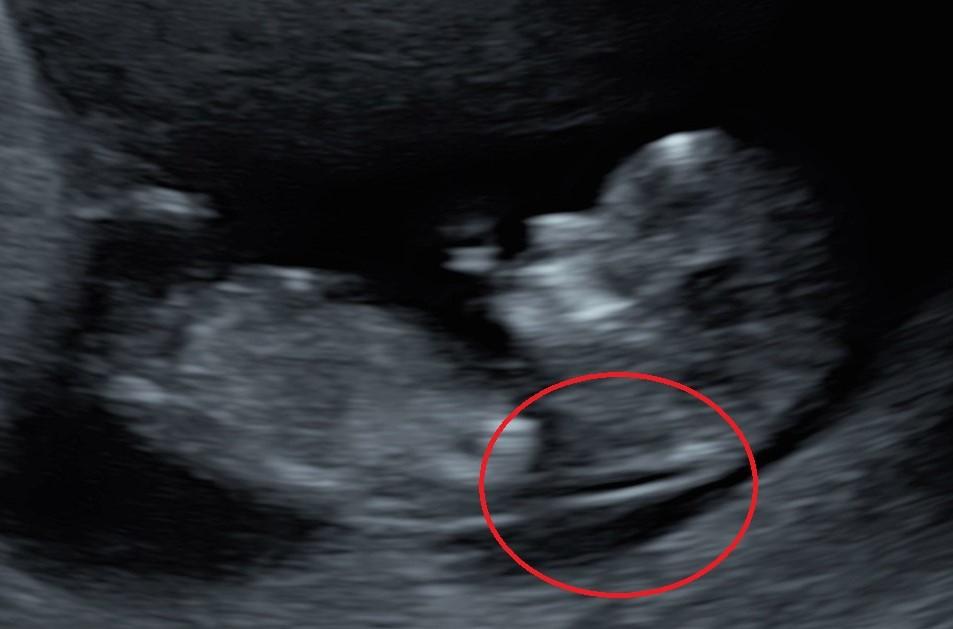

3.1. Tuần 6 – 8: Xác nhận thai trong tử cung và kiểm tra tim thai

Đây là mốc khám thai định kỳ đầu tiên, thường được gọi là “lần khám xác nhận thai”. Bác sĩ sẽ tiến hành siêu âm đầu dò để xác định vị trí làm tổ của phôi thai, loại trừ khả năng thai ngoài tử cung và ước tính chính xác tuổi thai. Đồng thời, ở giai đoạn này, tim thai bắt đầu xuất hiện, dấu hiệu cho thấy thai đang phát triển bình thường.

Tại Khoa Sản FV Thomson, bác sĩ kết hợp siêu âm 2D với xét nghiệm β-hCG nhằm đánh giá sự phát triển của phôi và chức năng hoàng thể. Đây cũng là thời điểm bác sĩ hướng dẫn mẹ về lịch khám thai định kỳ, chế độ dinh dưỡng, nghỉ ngơi và cách bổ sung axit folic để giảm nguy cơ dị tật ống thần kinh.